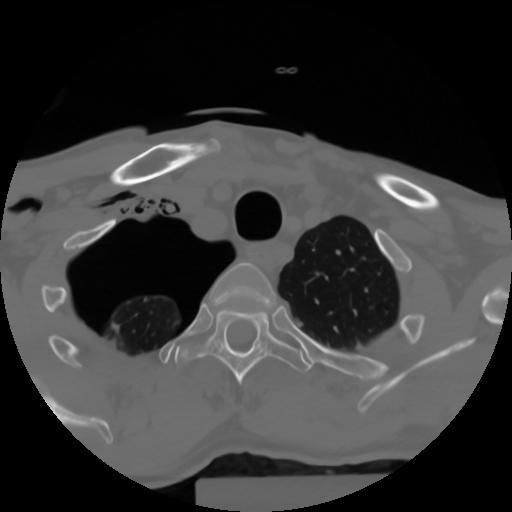

10 P.BLANDAS,,Axial,2.0,P.BLANDAS,,